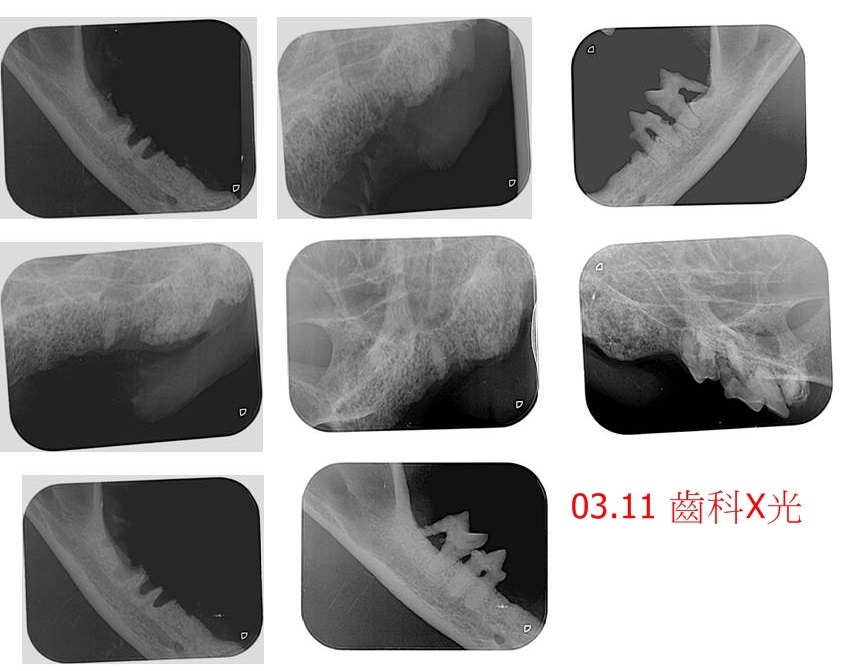

2月時,因舌頭潰瘍、口腔紅腫不適使鮮草流口水情況變得嚴重,沐恩醫師認為須做牙周手術,但因鮮草的心臟輪廓有些不正常,於是先至專心醫院檢查、確定鮮草可接受麻醉,即安排於3月11日進行牙周手術及採樣,如採樣結果無問題,再視術恢復情況,評估是否加入蘇醫師主持的干擾素計畫。

本筆醫助是鮮草於2月21日至3月26日間至沐恩醫院的看診費用,包含血檢、採樣、病理報告、牙周手術、齒科X光、口服藥等,鮮草之前流浪的生活好辛苦,讓他健康嚴重受創,往後的醫療還須很長一段時間,請大家一起幫忙鮮草,謝謝大家。

今天進行牙周手術及採樣。

目前看起來流口水的原因主要是牙齒的問題,口腔的紅腫並不嚴重,預計二週後回診以及採樣報告出來之後,再決定是否加入干擾素計畫。請留意鮮草流口水的狀態是否有改善。